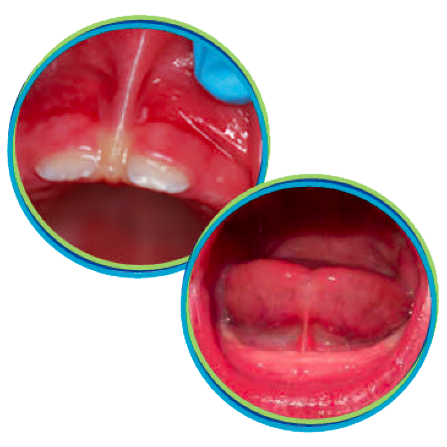

Laser Tongue Tie & Lip Procedures

We now offer laser tongue tie and lip tie services for your little ones!

Lip and Tongue Ties